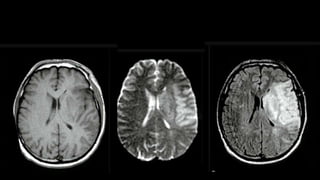

• #46 Here is the example of the same patient shown before. DWI shows hyperintensity in the right frontoparietal region with hypointensity on corresponding ADC map s/o diffusion restriction

• #47 MR 2D ANGIO and 3D TOF MIP images show loss of flow related signals in right MCA. RIGHT ICA appear decreased in calibre as compared to left ICA